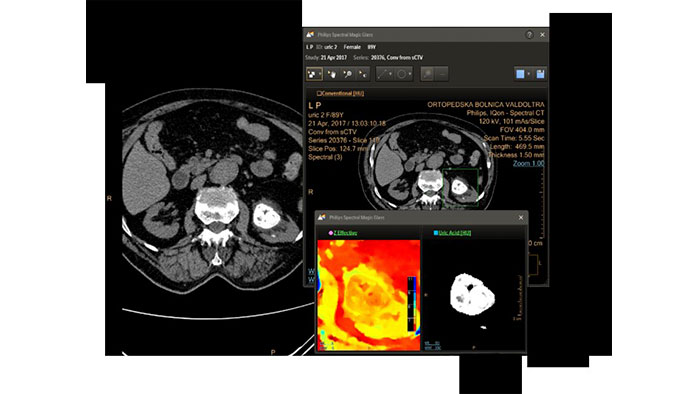

CT Spectral Light Magic Glass

Review spectral data in a range of not spectral-enhanced CT applications

Allows retrospective use of spectral data that was saved in a series of spectral base images (SBI).

The fast launch of LMG allows review and identification of the most relevant results to be launched into the application for further analysis.

Benefits

- The option is available from the following applications: Brain Perfusion, Functional CT, Liver Analysis, PAA, TAVI, Acute Multifunctional Review, Virtual Colonoscopy.

- Spectral Magic Glass can be launched only for CT images or images created on the Philips IQon Spectral CT.

CT Spectral Magic Glass on PACS*

IQon Spectral CT Functionality

IQon Spectral CT is the only scanner to offer CT Spectral Light Magic Glass and CT Spectral Magic Glass on PACS, helping radiologists review and analyze multiple layers of spectral data at once, including on their PACS.

Benefits

- On-demand simultaneous analysis of multiple spectral results for an Region Of Interest (ROI).

- Integrates into a health system’s current PACS setup for certain PACS vendors.

- Spectral results viewable, during a routine reading.

- Enterprise-wide spectral viewing and analysis allows access to capabilities virtually anywhere in the organization.

* Standard with the CT Spectral option on IntelliSpace Portal.